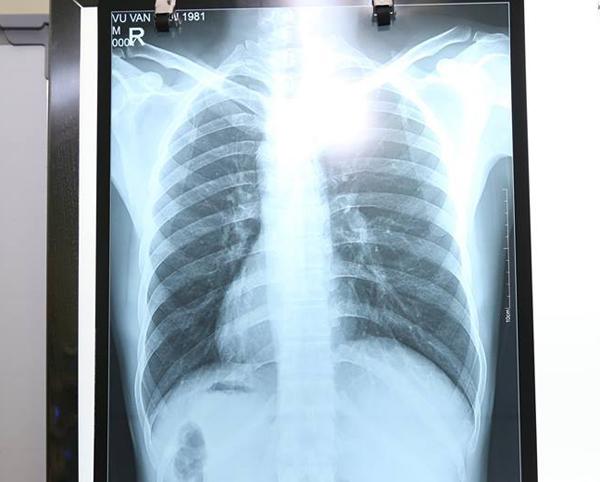

Tuy nhiên, điều khiến các bác sĩ kinh ngạc là tim cùng các phủ tạng khác trong lồng ngực và bụng của bệnh nhân đều ở vị trí ngược so với bình thường, tim và dạ dày đều ở bên phải còn gan, ruột thừa nằm ở bên trái.

Tim, dạ dày và nhiều cơ quan nội tạng khác của bệnh nhân H. đều ở vị trí lộn ngược so với người bình thường